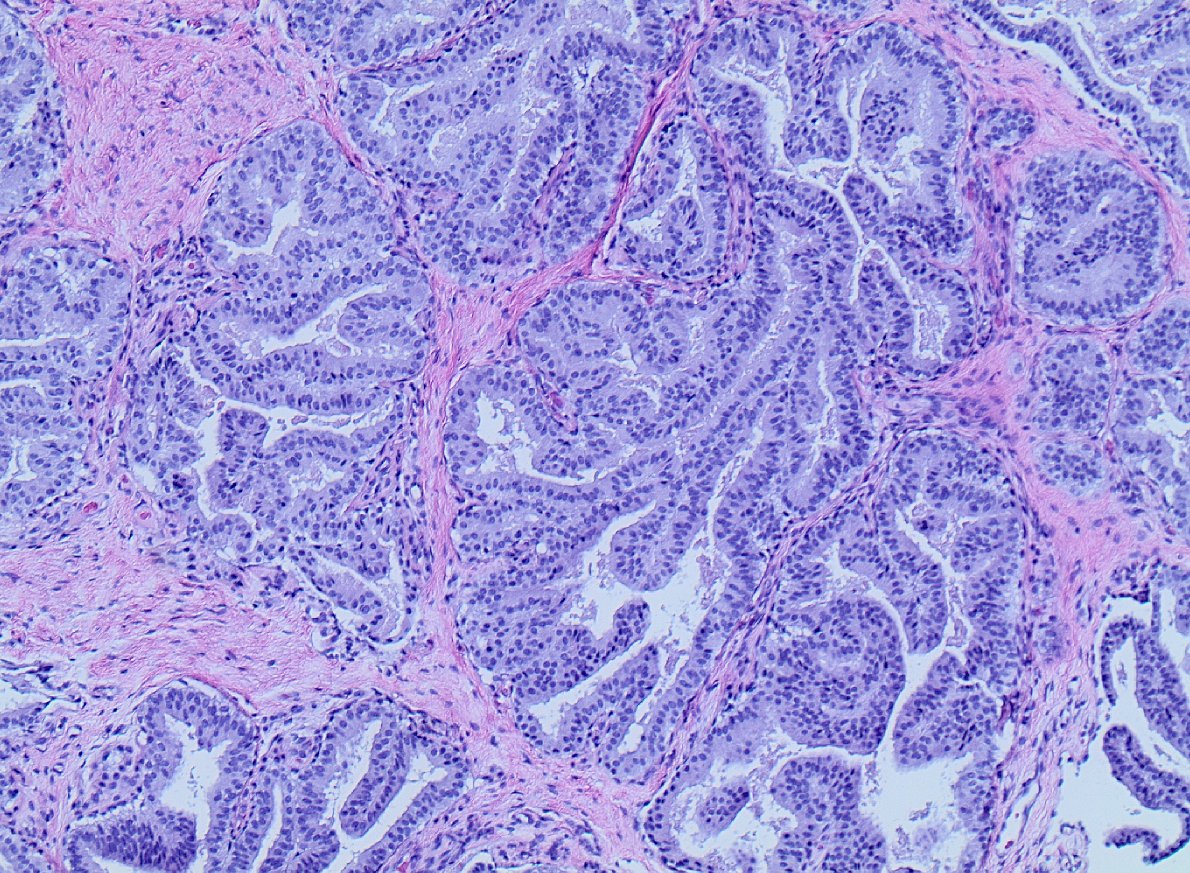

Liver metastasis in adult. Diagnosis? AE1/AE3 and Ki67 in next tweet. Can you tell the origin of the tumour? #pathology

10

14

53